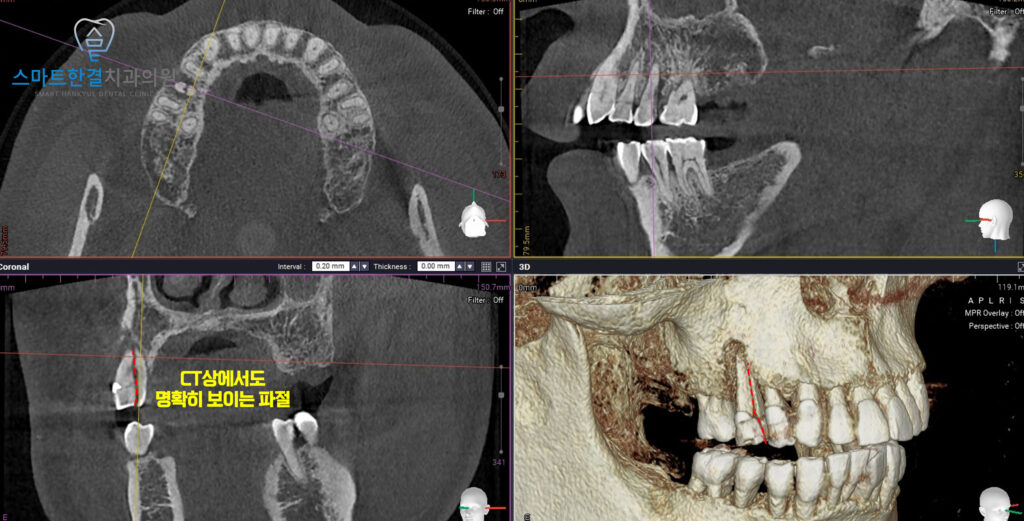

먼저 CT 촬영을 통해

뼈의 높이·두께 등을

정밀하게 확인한 뒤,

임플란트 식립을 위한

전반적인 조건을 체크했어요.

CT상에서도 파절을

확인할 수 있었어요.

촬영 결과를 바탕으로

임플란트를 식립하기로 했답니다.